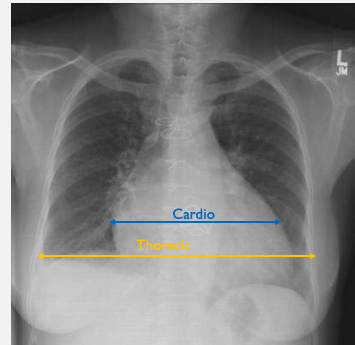

• Heart size: Normal cardiothoracic ratio ≤ 0.5

Pleural effusion Pulmonary oedema **Cardiomegaly** Normal CXR